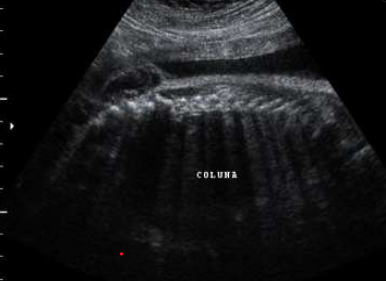

A ultrassonografia tridimensional tem se mostrado uma ferramenta importante para

diagnóstico das malformações Müllerianas. Em relação a imagem abaixo assinale a hipótese diagnóstica e qual a outra estrutura que deverá ser examinada?